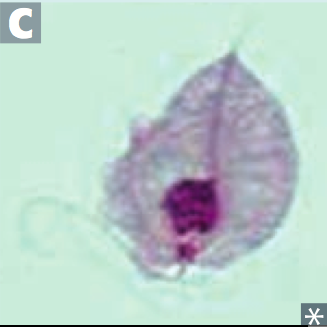

Trichomonas vaginalis